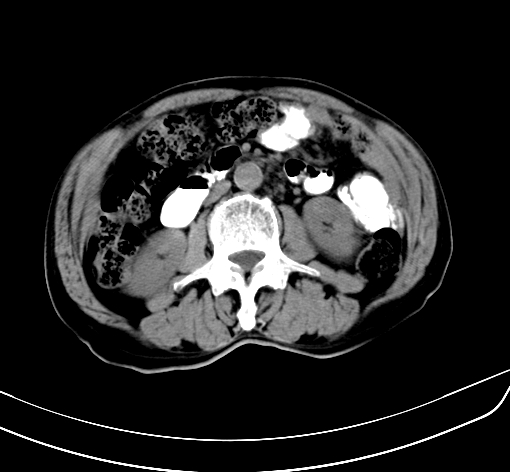

病人 男 70 咳嗽 胃部不适 2月余

胆囊壁增厚,与临近肝实质边界不清,临近肝实质内可见大片边界不清之低密度区,肝门区密度亦有减低,部分结构不清,尾叶前方可见块状影,肝右叶可见多枚边界不清之圆形低密度区,肝内胆管扩张征象,结合病史考虑1胆囊癌肝内转移,肝门区淋巴结转移,门脉癌栓待排2肝内胆管扩张3建议增强扫描

肝脏多发大小不等低密度灶,边界不清,肝门区结构不清,肝内胆管轻度扩张,胆囊密度不均匀,内见软组织样密度影,与相临肝脏边界不清.考虑:1、胆囊ca侵犯肝脏并肝内多发转移,肺上也有结节影,转移?建议强化扫描.2、胃充盈不好,如怀疑有病变最好建议做相关检查.

胆囊壁增厚,周围模糊不清,肝内多发低密度影,胃充盈欠佳,胃壁增厚,外形尚规整,考虑胆囊炎、胆囊癌肝内转移?建议胃肠道进一步检查或增强扫描。